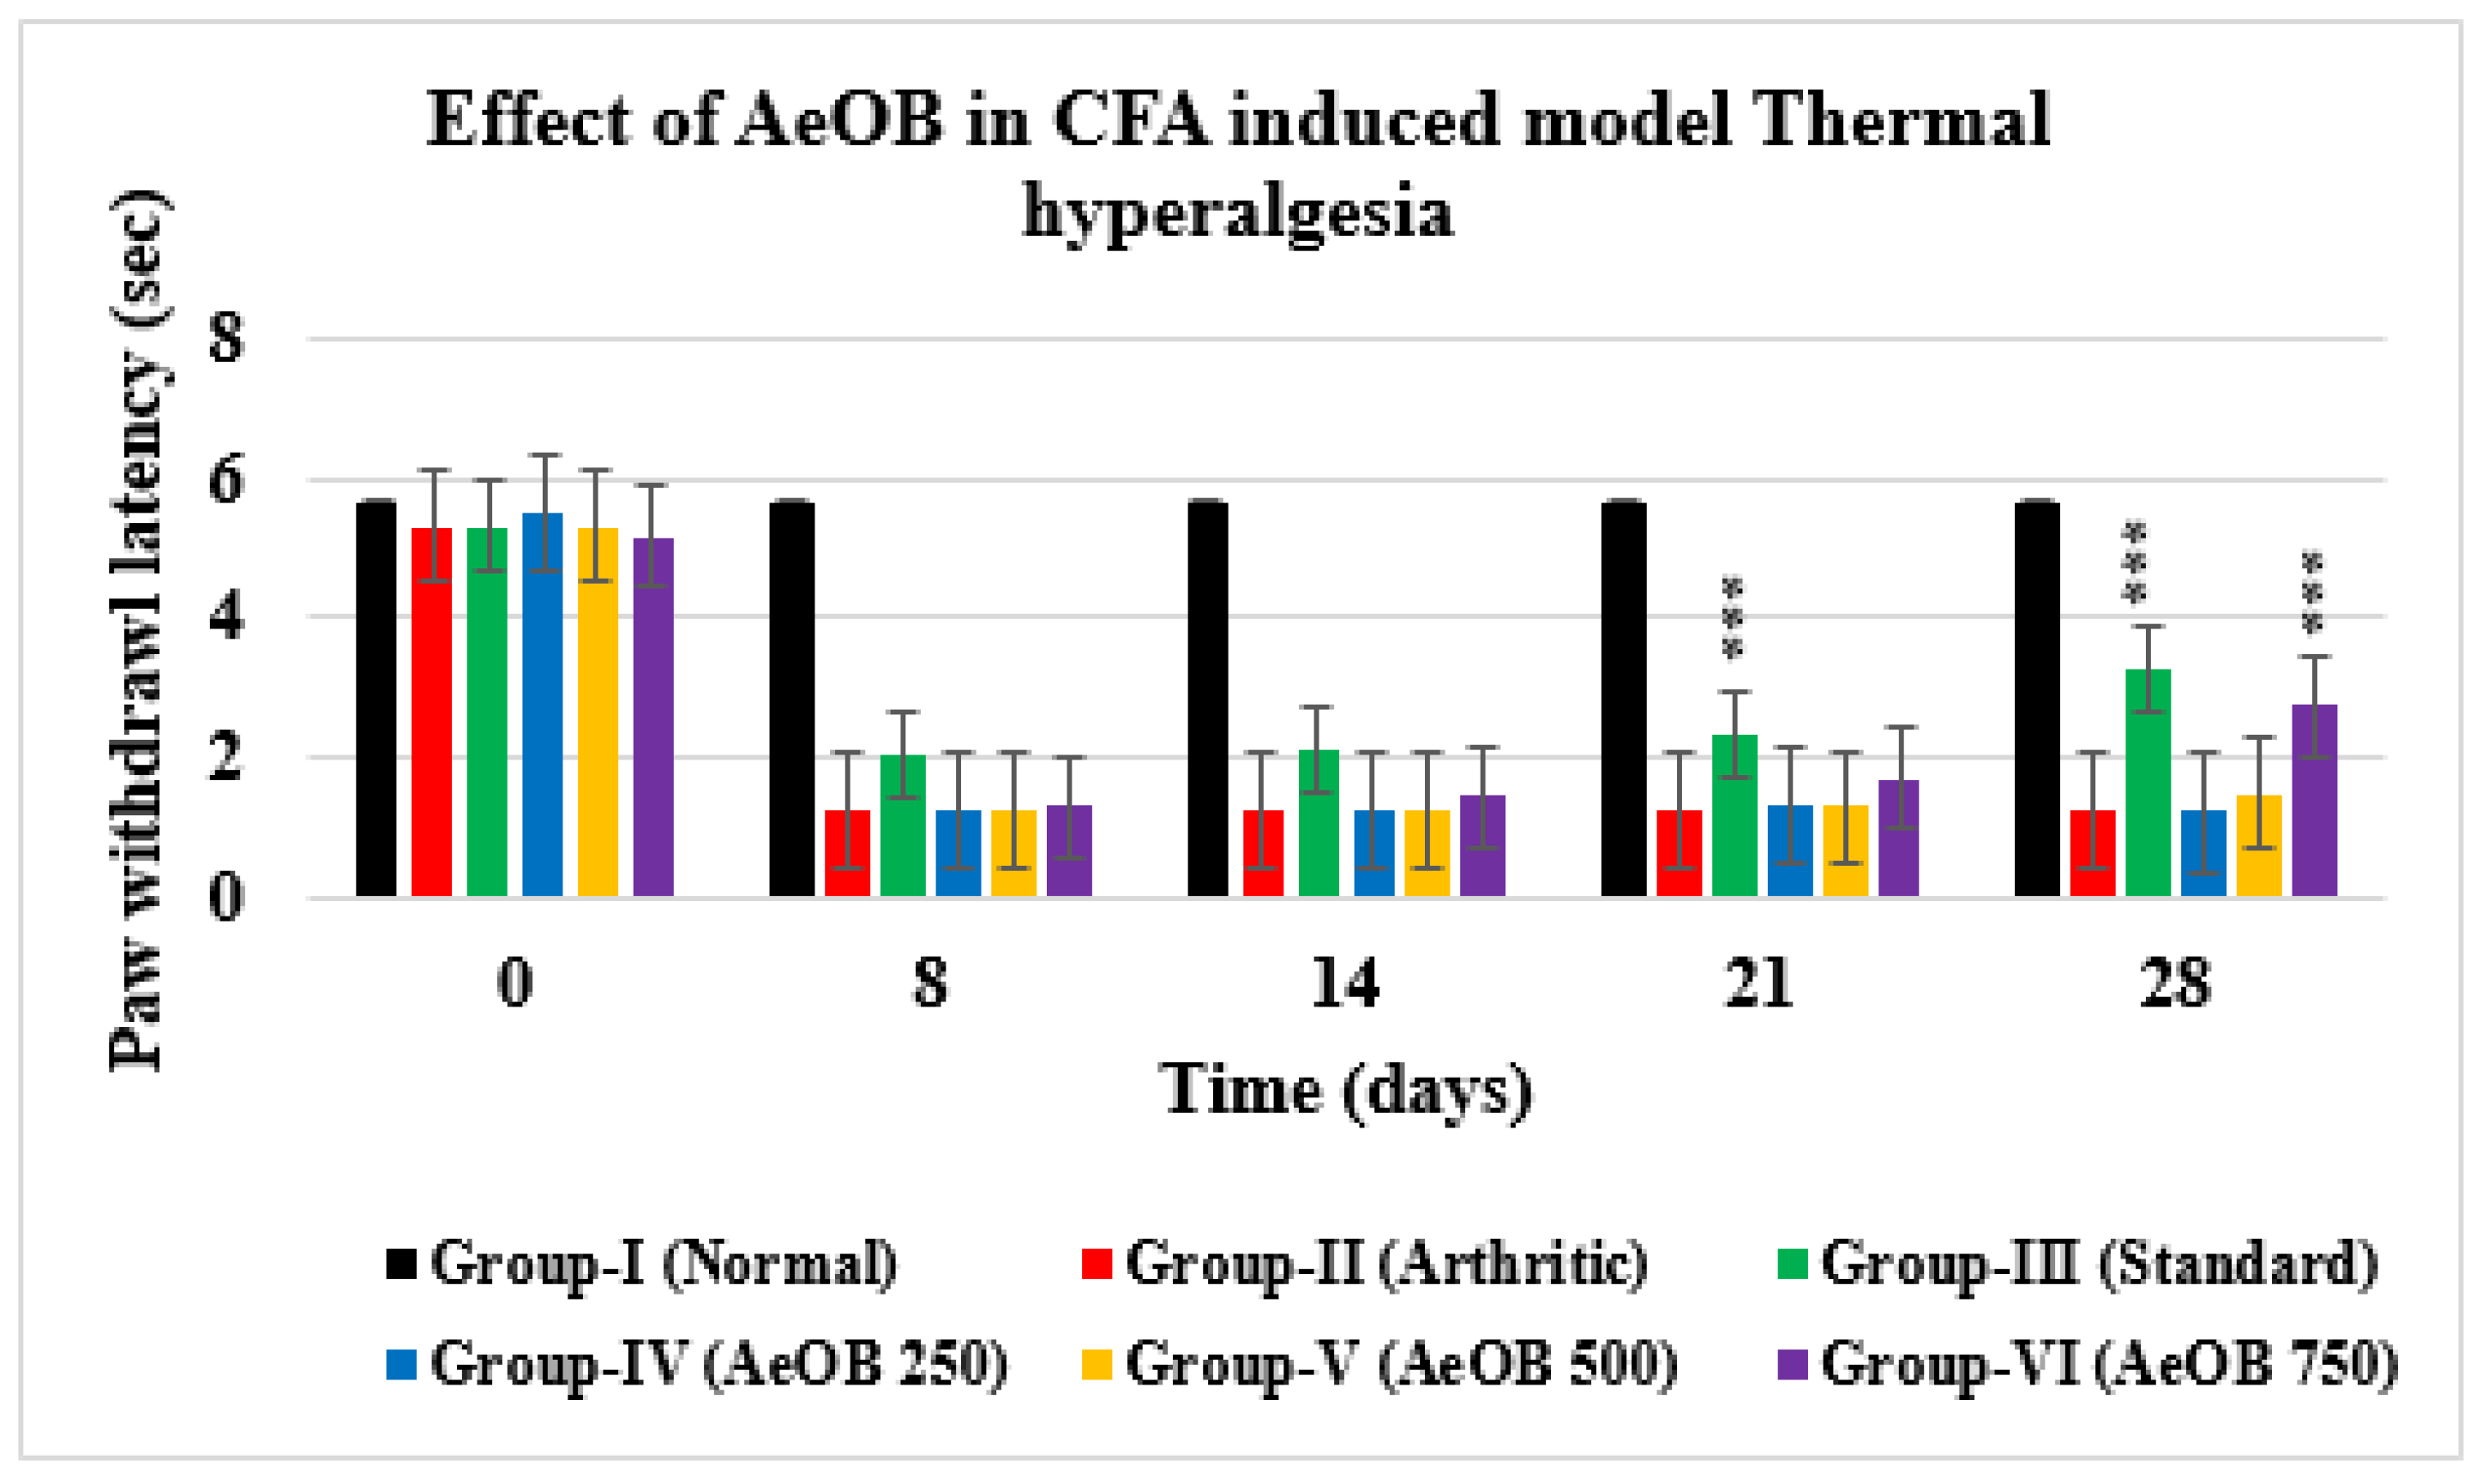

2.6.2. Hot Plate/Thermal Hyperalgesia

4.7.8. X-ray and Histopathology